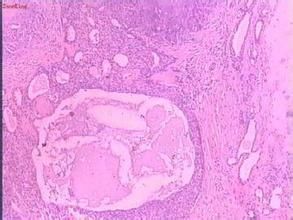

真皮內見由立方形或多角形上皮細胞形成的巢呈管泡狀和導管結構偶可形成角囊腫此種結構被包埋在淡藍色軟骨樣物質到嗜酸性透明物質的基質中。治療